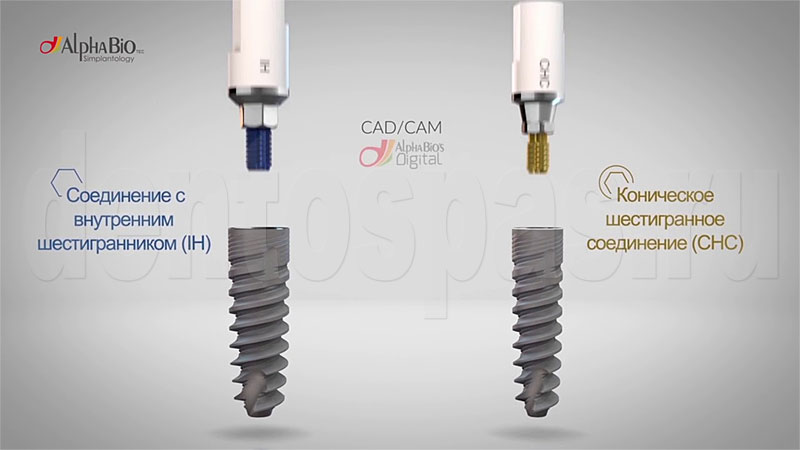

Рентген имплантов Alpha Bio: диагностика и качество